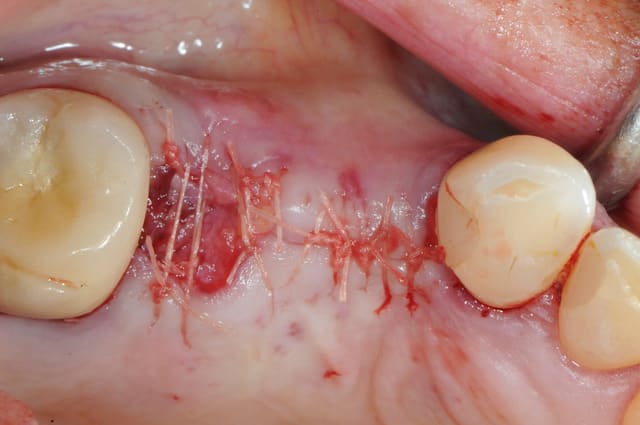

le cas que je vous présente date d'hier, il n'a rien d'extraordinaire, alors soyez indulgents, c'était juste pour le plaisir de partager ça avec vous.

ici, tu l'as compris, ce n'est pas vraiment nécessaire excepté pour la 2 ième prémolaire où l'extraction est très récente (2 mois à peine) et où l'alvéole à été comblée par un biomatériaux.